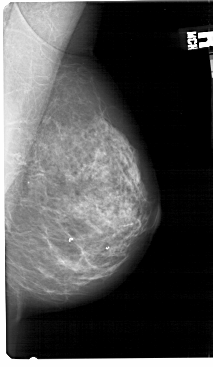

A_1362_1.LEFT_MLO

LEFT_MLO LINES 5491 PIXELS_PER_LINE 3106 BITS_PER_PIXEL 12 RESOLUTION 43.5 OVERLAY